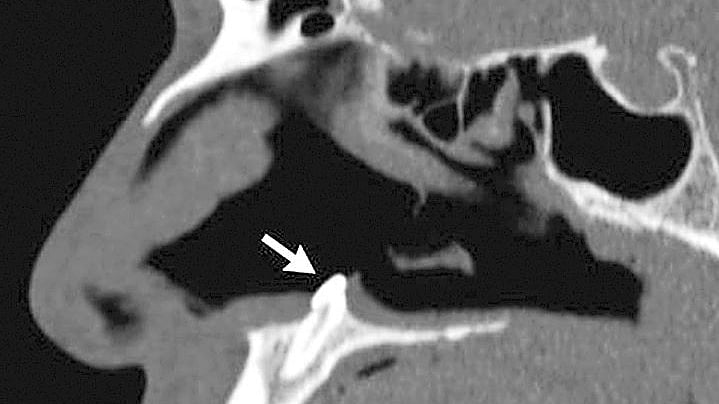

নাকের ভেতরে আস্ত একটি দাঁত গজিয়ে উঠছিল নিউইয়র্কের ওই ব্যক্তির।

এরপর ওই ব্যক্তির শ্বাসতন্ত্রের পরীক্ষা–নিরীক্ষা করা হয়। তবে তাতে কোনো সমস্যা পাওয়া যায়নি। চিকিৎসকেরা ওই ব্যক্তির ডান নাক দিয়ে ক্ষুদ্র আকারের একটি ক্যামেরা প্রবেশ করান। এতে তাঁর নাকের ভেতরের অংশে একটি দাঁত গজাতে দেখা যায় বলে জানিয়েছে ইউপিআই। আর এ দাঁতের কারণে ওই ব্যক্তির শ্বাসকষ্ট হচ্ছিল।

ঘটনাটি নিয়ে নিউ ইংল্যান্ড জার্নাল অব মেডিসিন–এ একটি নিবন্ধ লিখেছেন ওই হাসপাতালের সার্জন সাগর খান্না ও মাইকেল টার্নার। তাঁরা জানান, ওই ব্যক্তির নাসারন্ধ্রের ভেতর একটি দাঁত ধীরে ধীরে গজিয়ে উঠছিল। এ কারণেই তাঁর শ্বাস নিতে সমস্যা হচ্ছিল।

পরে চিকিৎসকেরা ওই ব্যক্তির ডান নাকের ভেতর থেকে প্রায় দশমিক ৬ ইঞ্চি লম্বা দাঁতটি তুলে ফেলেন। এতে কোনো সমস্যা হয়নি। এখন তিনি সুস্থ আছেন। চিকিৎসকের পরামর্শে বাসায় আছেন। তিন মাস পর তাঁকে আবারও চিকিৎসকের শরণাপন্ন হতে পরামর্শ দেওয়া হয়েছে।